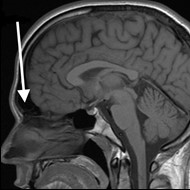

Na obrazie TK zaznaczono zatokę

Ilustracja do pytania 16

A. czołową w przekroju czołowym.

B. czołową w przekroju strzałkowym.

C. szczękową w przekroju strzałkowym.

D. szczękową w przekroju czołowym.